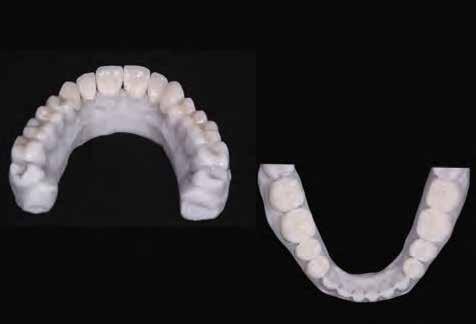

A laboratóriumban szekciós minta készült, blokk-stiftekkel (1. kép) , amelynek készítése során nagy figyelmet szenteltünk az ínymaszk (Majesthetik- Gingiimplant picodent) és a felfekvő lengőtag területének (2–6. képek)

A minta beolvasása után számítógéppel terveztük meg a híd vázát (7. kép). 0,06 mm-es cementrést terveztünk a teljes karfelület alá, 1 mmre végződve a preparáció szélétől (8–11. képek)

Így egyenlítettük ki a kötésjavító vastagságát, sikeresen. Az adatokat elküldtük az AHRtec-frézközpontba, néhány nap múlva visszakaptuk a cirkonvázat (12. kép). A marási paraméterek optimális betartása következtében a passzítás egyszerű volt (13. kép)